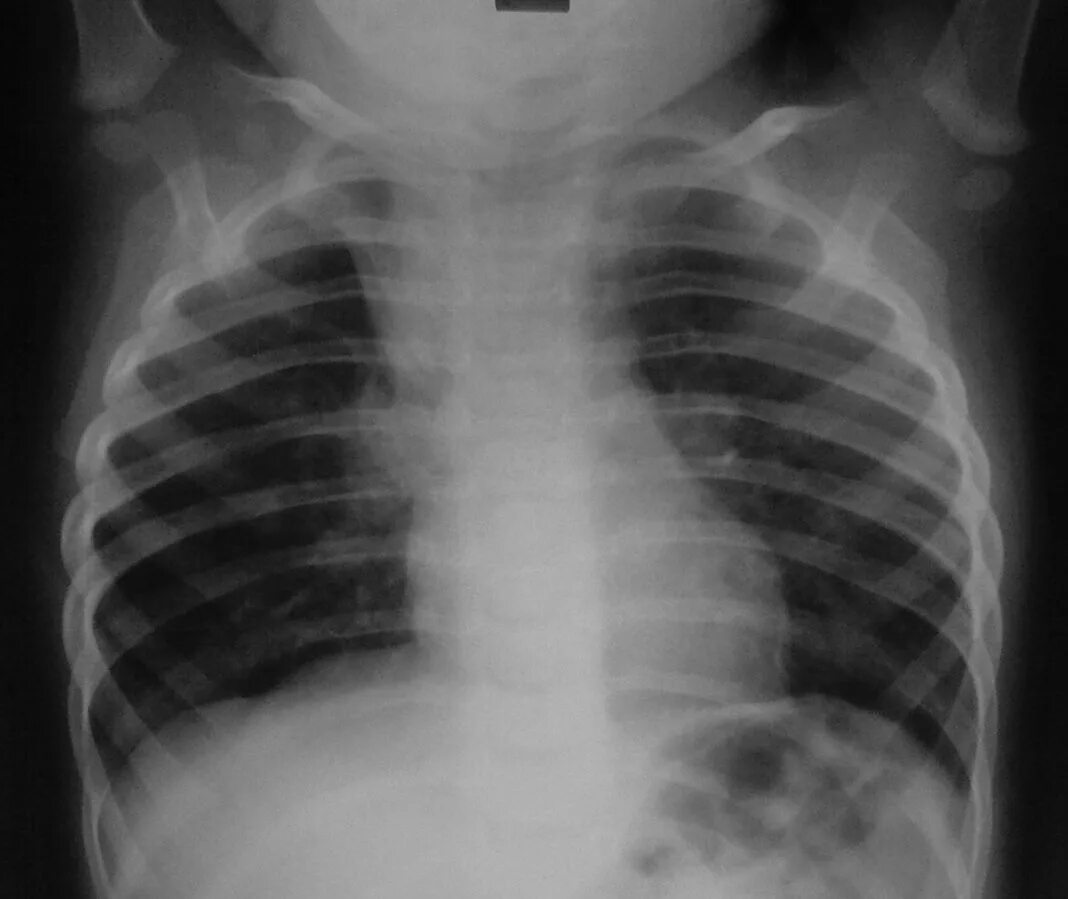

Диффузный эндобронхит